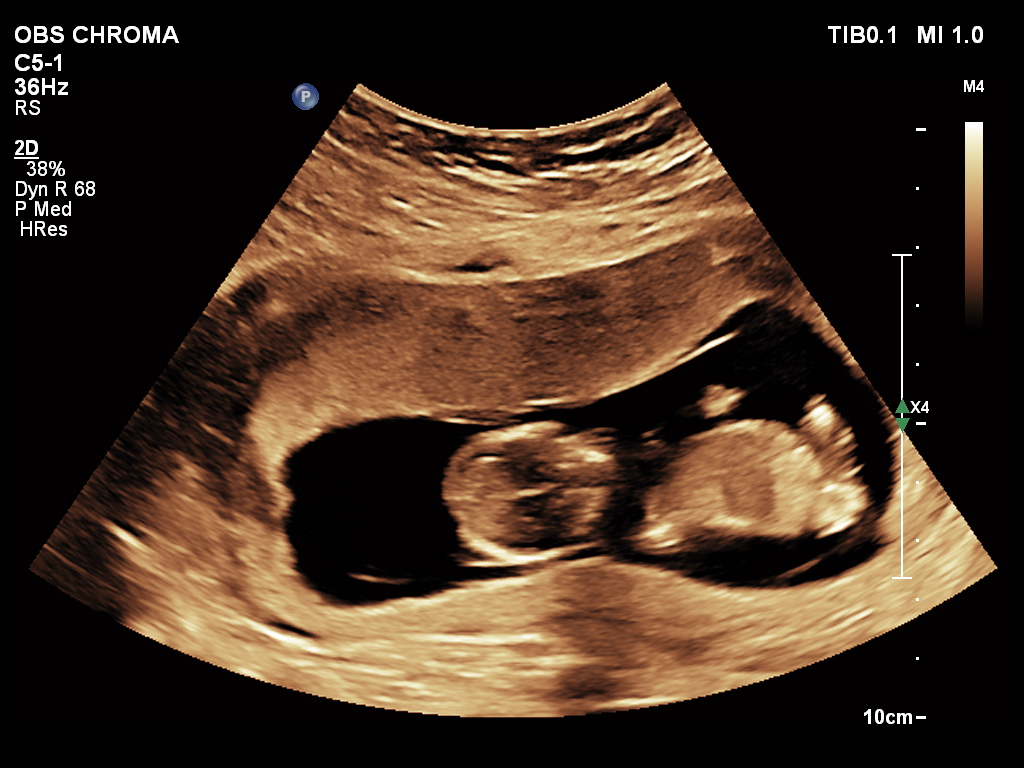

🔹 3D / 4D Ultrasound

3D/4D Ultrasound provides a clear and real-time view of your baby inside the womb. While 3D shows detailed images, 4D allows you to see live movements like smiling or yawning. It enhances bonding between parents and baby while also helping doctors assess physical development. Experience advanced 4D ultrasound in Kathmandu for a memorable and informative pregnancy journey.